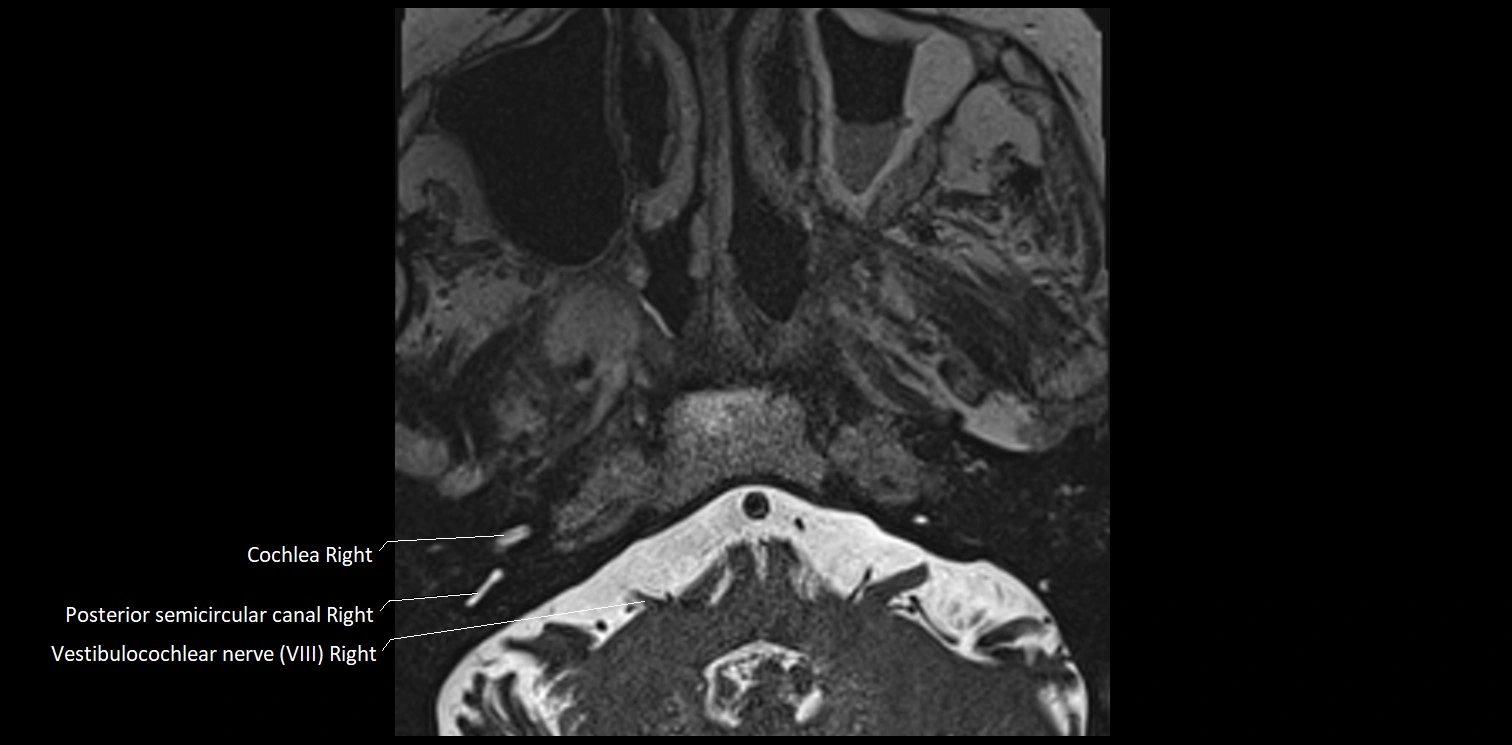

MRI images

image